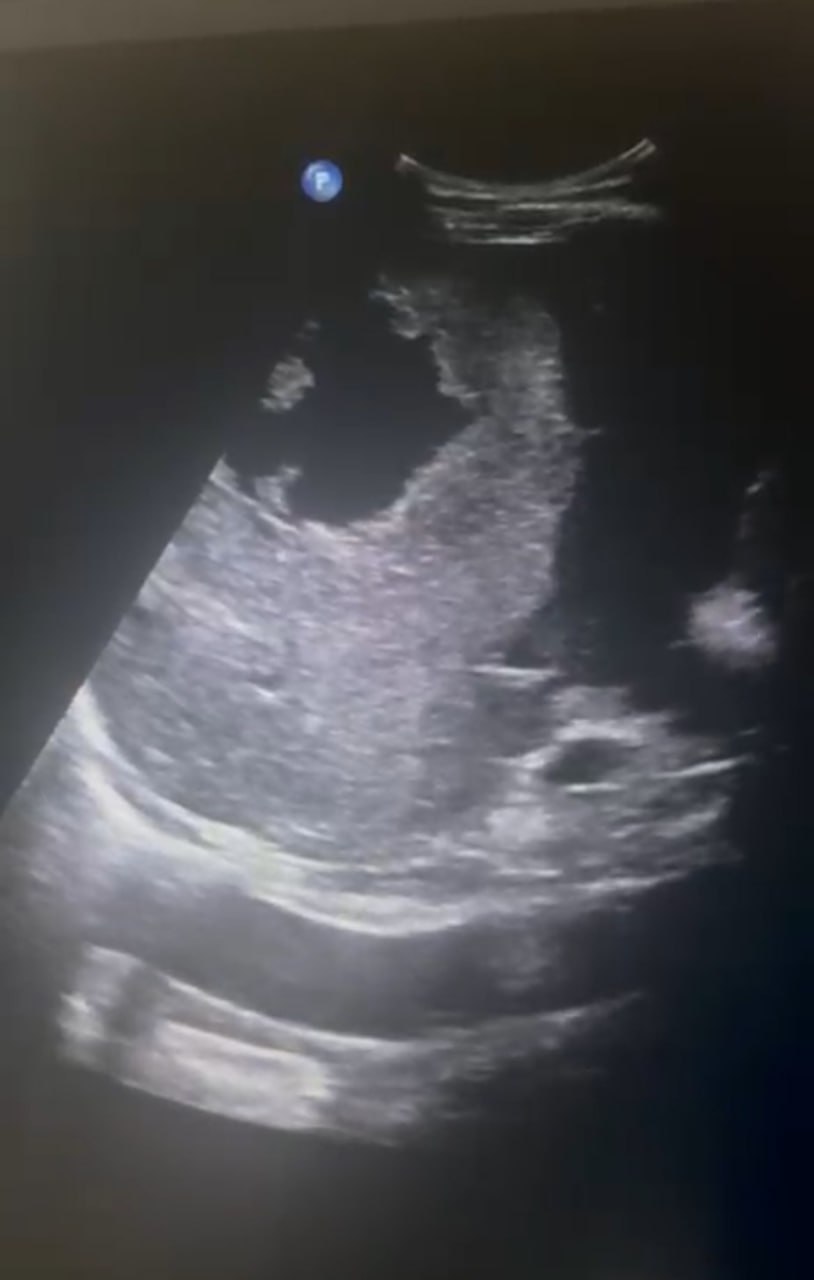

«День спустя: чётко видна зона гематомы — тёмное, неоднородное пятно. Неделя спустя: пятно стало меньше, его контуры — более чёткими. Гематома начала рассасываться. Контрольное УЗИ: улучшения. Острая фаза миновала, угрозы для жизни больше нет Выписка стала возможной только после этого заключения», — рассказали в минздраве СК.